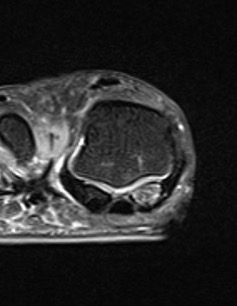

CT demonstrates irregular borders consistent with fracture of tibial sesamoid

Edema on T2 MRI indicates likely acute fracture